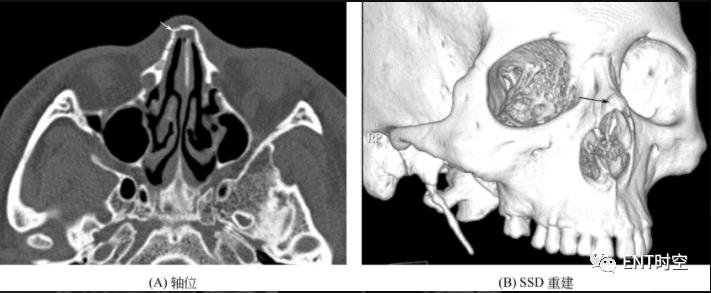

1.症状 外鼻肿胀和畸形、鼻出血、鼻部疼痛、头痛、头晕,严重者可出现脑脊液鼻漏及休克症状。 2.体征 (1)鼻骨骨折可引起外鼻畸形,如外鼻歪斜或下榻,外鼻平坦。软组织挫伤,鼻部和眼睑部淤斑。有皮下气肿时,外鼻触诊可有捻发音。鼻腔内流清水样分泌物可能为脑脊液鼻漏。(2)鼻腔内检查可发现鼻黏膜损伤、鼻出血、鼻中隔偏曲及血肿。 3.辅助检查 (1)鼻骨X线平片作为初步检查方法;(2)CT最可靠,能够准确判断骨折类型、骨折断端移位方向及程度和邻近结构骨折。另外,SSD图像能直观地显示骨折情况。见下图。

图 鼻骨骨折

(A)示右侧鼻骨骨质中断、成角;(B)立体显示骨折情况